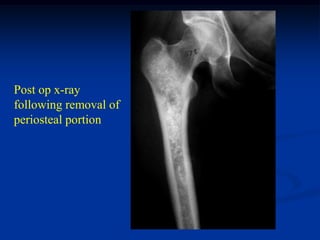

Post op x-ray

following removal of

periosteal portion